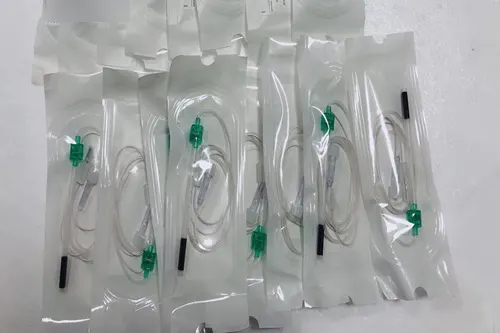

外周神经丛刺激针同品种比对产品注册案例

三类器械注册